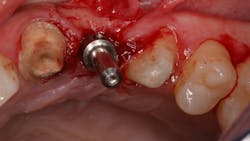

A quick clinical intervention to rectify incorrect initial osteotomy preparation can be accomplished with a Lindemann bur. A Lindemann bur is a side-cutting bur used to move pilot preparation in a bodily manner with ease and without the likelihood of further angulation issues (figure 4). After initial pilot drilling, a radiographic locator is placed to check position. If the radiographic index is shown to be incorrect, under copious irrigation, place a Lindemann bur in the osteotomy parallel to the intended location and move in a rigid upright fashion to the ideal location. Take a radiograph to verify correct position.